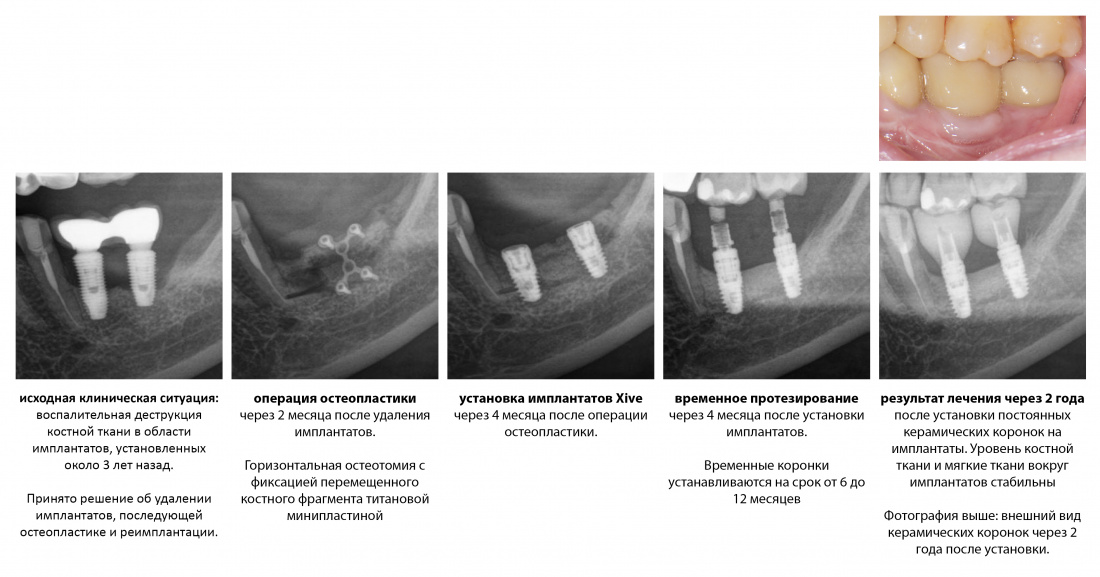

Кстати, о клиническом случае на этой картинке вы можете пjочитать здесь>>